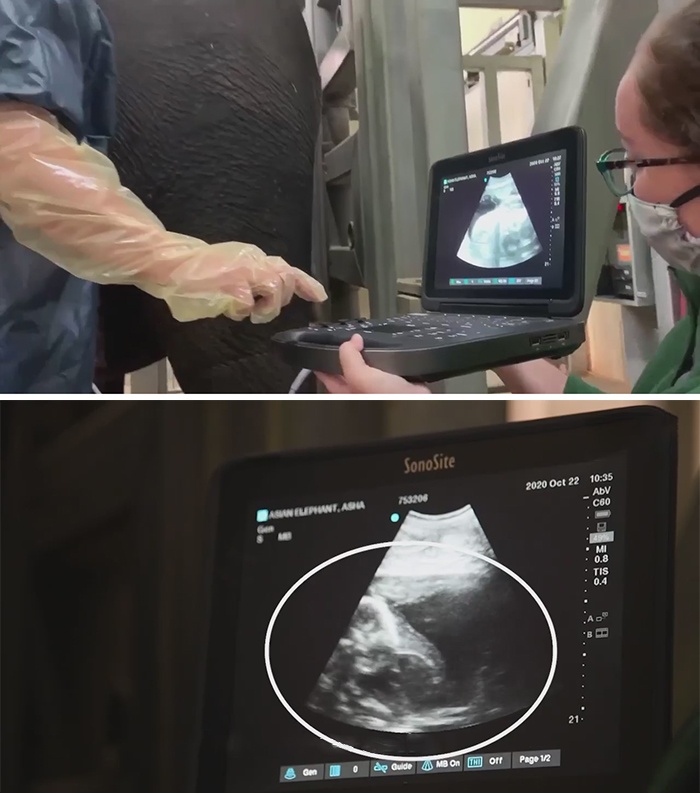

Pravidelnou metódou na kontrolu gravidity slona sú ultrazvuky, ktoré vykonáva veterinárny tím zoo. Posledný ultrazvuk – ten, ktorý je viditeľný aj vo videu nižšie – ukázal, že matka aj dieťa sú úplne zdravé. Na rozdiel od ultrazvukov vykonávaných na ľuďoch, ktoré sa častokrát veľmi ťažko rospoznávajú, je tento prekvapivo jasný. Hlava, chobot aj nohy sú veľmi ľahko a dobre viditeľné. A je to veľmi milé sledovať.